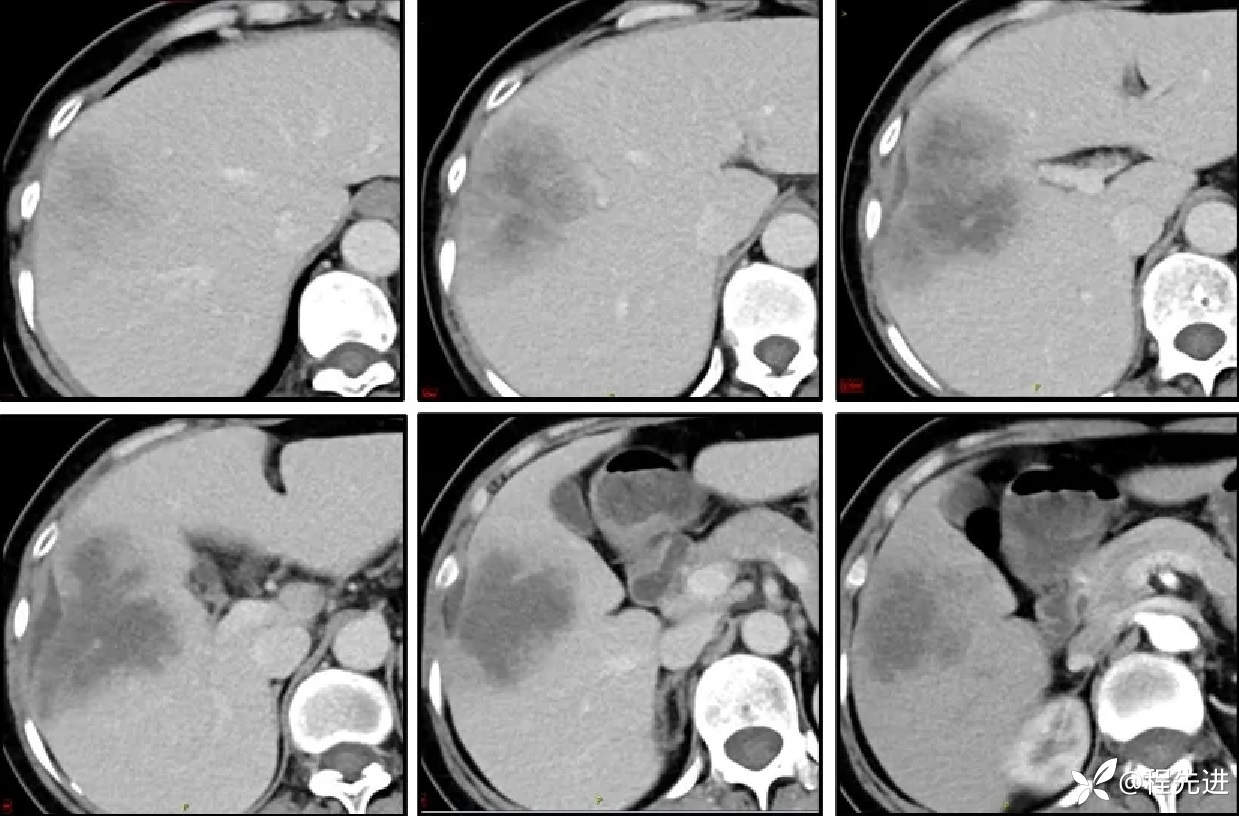

CT增强,3期: